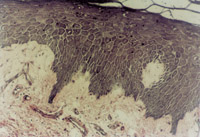

治療30天后,創(chuàng)面上皮組織再生修復(fù)良好(圖5-3-5),皮膚結(jié)構(gòu)已經(jīng)基本正常(圖5-3-6)。

5-3-6 治療30天后的創(chuàng)面其表皮組織,真皮組織結(jié)構(gòu)已呈生理狀態(tài)  HE×20